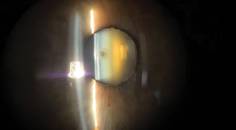

Just 4 years ago we were unable to simultaneously correct astigmatism and presbyopia at the time of cataract surgery. Now the PanOptix IOL can correct a patient’s distance, intermediate, and near vision, in addition to astigmatism with the toric version (Figure). This technology has been available in markets outside the United States for more than 5 years, but we are going to take a look at how the PanOptix lens has performed inside the United States over the past year.

Figure. A toric PanOptix IOL immediately after refractive laser cataract surgery. As seen here, the IntelliAxis (LensAR) marks the anterior capsule to enable precise toric IOL alignment, allowing easy evaluation both intra- and postoperatively.